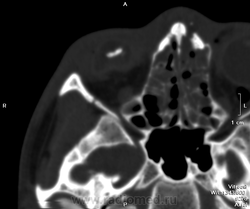

Перелом по Ле Фор-2. Спасибо за ссылку, Nela!

Людмила Григорьевна, именно - ЛеФОР II

А не Ле Фор-III? Плоскость перелома-то проходит через латеральные стенки орбит и решетчатый лабиринт... Краниофациальная дизъюнкция, вроде бы.

ЛефорI (верхний тип) – линия перелома проходит через носолобный шов, по внутренней стнке глазницы до места соединения верхне– и нижнеглазничной щелей.

ЛефорII (средний тип) – линия перелома проходит в месте соединения лобного отростка верхней челюсти с носовой частью лобной кости и костями носа.

ЛефорIII (нижний тип) – линия перелома проходит в горизонтальной плоскости над альвеолярным отростком и сводом твердого неба.

В направлении II, выставил I.

В случае Сергея Викторовича, справа тип 1, слева тип 3. Меня учили, что только двусторонний тип отрыва лицевого скелета можно называть переломом по Ле Фор 3.

В интернетовских ссылках тоже путаница с 1 и 3 типами. Но мне кажется правильным называть первый тип - нижним.

Наши стоматологи-хирурги называют переломом по Ле Фор-III именно "верхний" тип. В тех книжках по рентгенологии, какие я видел, было точно так же.

Почему я подумал про III: мне кажется, справа тоже перелом.

Павел, кажется, Вы правы. Пусть будет "верхний" Ле Фор